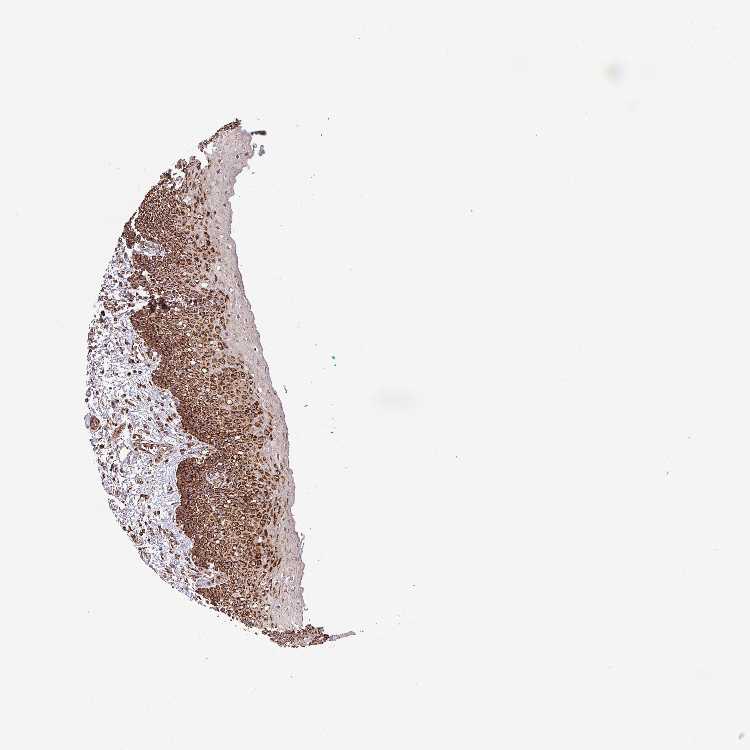

TISSUE PRIMARY DATA ORAL MUCOSA Show tissue menu

ORAL MUCOSA - Antibody stainingi

Antibody staining in the annotated cell types in the current human tissue is reported as not detected, low, medium, or high, based on conventional immunohistochemistry profiling in selected tissues. This score is based on the combination of the staining intensity and fraction of stained cells.

Each image is clickable and will lead to virtual microscopy that enables deeper exploration of all samples and also displays staining intensity scores, fraction scores and subcellular localization as well as patient and tissue information for each sample.

Antibody HPA041082Antibody HPA044227

Squamous epithelial cells HighHigh